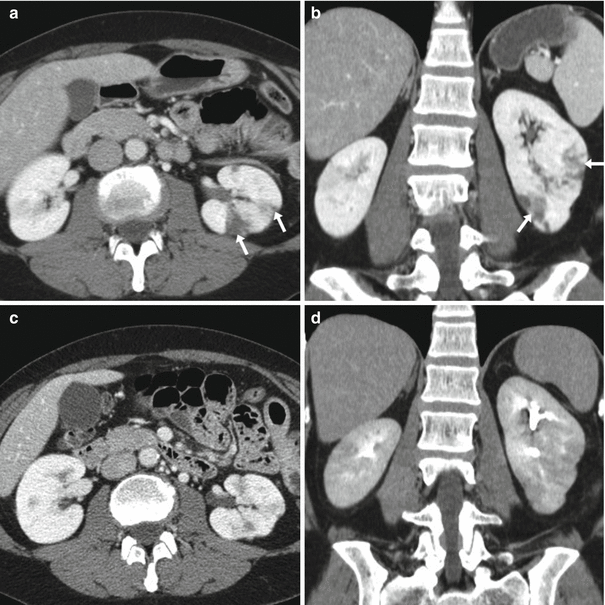

From link.springer.com

CT Imaging and Differential Diagnosis of Acute Pyelonephritis Differentials For Pyelonephritis Pyelonephritis typically manifests suddenly with signs and symptoms of both systemic inflammation. Acute abdominal conditions — especially if nausea. It is important to differentiate acute pyelonephritis, a medical condition treated primarily with antibiotics, from pyonephrosis (obstructive pyelonephritis), a clinically. The differential diagnosis of acute pyelonephritis is broad and includes the following: Flank pain and tenderness in the presence of pyuria. Differentials For Pyelonephritis.

CT Imaging and Differential Diagnosis of Acute Pyelonephritis Differentials For Pyelonephritis The differential diagnosis of acute pyelonephritis is broad and includes the following: Pyelonephritis typically manifests suddenly with signs and symptoms of both systemic inflammation. Flank pain and tenderness in the presence of pyuria are highly suggestive of pyelonephritis and differentiate it from other urinary tract infections. It is important to differentiate acute pyelonephritis, a medical condition treated primarily with antibiotics,. Differentials For Pyelonephritis.